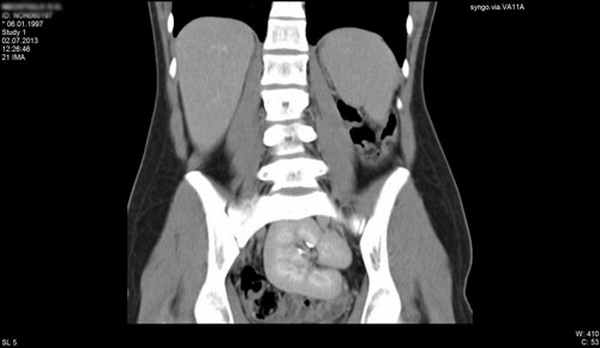

В Национальном медицинском исследовательском центре имени В. А. Алмазова функционирует Научно-исследовательская лаборатория (НИЛ) детской эндокринологии, клинической базой которой является педиатрическое отделение. Сотрудники НИЛ, являющиеся одновременно врачами-детскими эндокринологами, имеют большой опыт оказания помощи пациентам с различной патологией полового развития, включающий поликомпонентное обследование (проведение стимуляционных и супрессивных тестов для уточнения функциональной активности половых желез, визуализационные методы, иммуногистохимическое обследование, молекулярно-генетическое и цитогенетическое обследование и др.). В команде с мультидисциплинарной группой специалистов Центра (гинекологи, урологи-андрологи, клинические и молекулярные генетики, детские хирурги, психологи и психотерапевты) проводится окончательная верификация диагноза и составляется долгосрочная программа ведения пациентов. При условии регулярного мониторинга осуществляется заместительная гормональная терапия, определяется прогноз фертильности, решаются вопросы, связанные с присвоением гражданского пола, мониторинга онкологического риска дисгенетичных гонад, объема и сроков хирургического лечения. Возможно биобанкирование биологического материала с целью сохранения фертильности. Среди пациентов Центра наблюдаются дети с полной дисгенезией гонад (синдром Свайер), полной и частичной резистентностью к андрогенам, нарушениями биосинтеза тестостерона, включая редкие формы врожденной гиперплазии коры надпочечников, пациентки со сниженным овариальным резервом, синдромом поликистозных яичников и многие другие. В перспективе части пациентов с нарушением формирования пола могут быть решены вопросы фертильности путем вспомогательных репродуктивных технологий. Оказание помощи пациентам базируется на персонифицированном подходе, который возможен на основе понимания индивидуальных характеристик, в том числе с позиции молекулярной генетики, варианта патологии у конкретного больного. На снимках представлены результаты обследования некоторых из наших пациентов, продолжающих наблюдаться в нашем Центре.

Синдром Рокитанского-Кюстнера-Майера-Хаузера у девочки 16 лет с первичной аменореей. МРТ органов малого таза. (агенезия матки, влагалища, тазовая дистопия единственной почки).

НФП – полная форма резистентности к андрогенам. МРТ органов малого таза (тестикулы в паховых каналах) у фенотипически девочки с кариотипом 46ХУ.